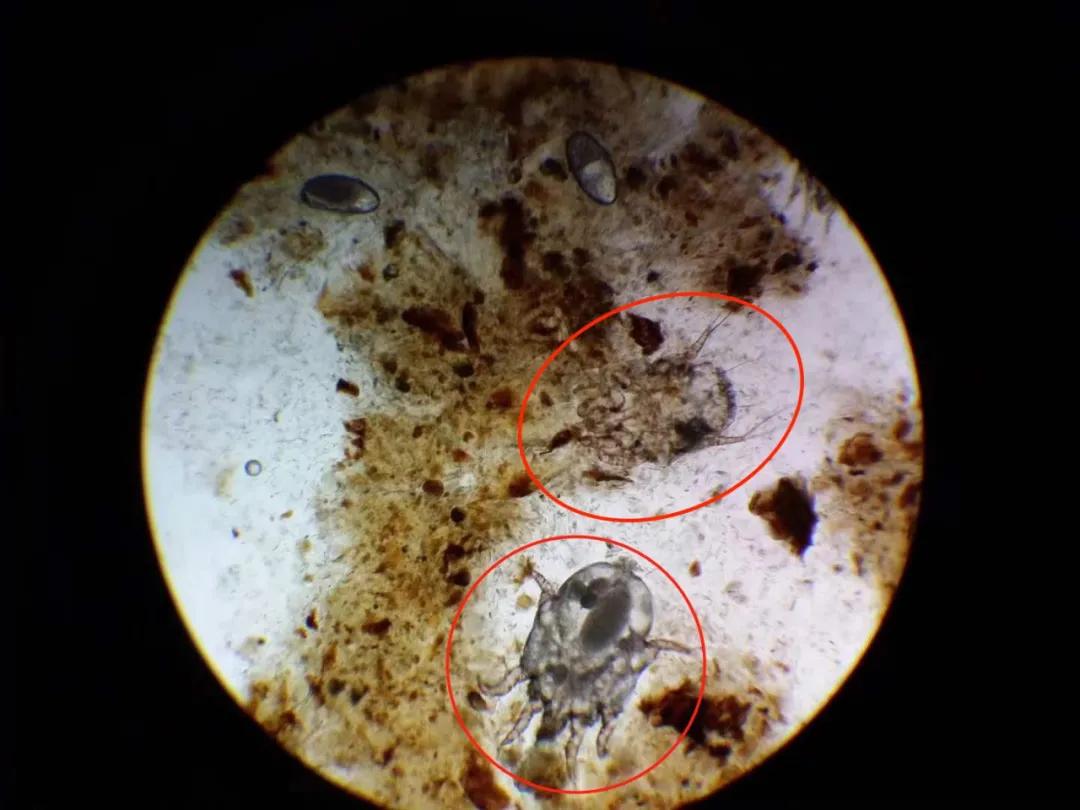

就像下面这样↓(图片可能会引起不适,可直接滑过)

看完他发来的照片后,我赶紧让他带着猫去医院做了检查。果不其然,这只猫咪得了 中耳炎耳螨 ,还继发了 细菌感染!

(在显微镜下看,大块大块的耳垢,和数只螨虫)

医生分析说,可能是耳朵里进了不干净的水,没有及时清洁干净。也有可能是宠物店洗澡的时候使用公共的洁耳液和工具被传染了螨虫。